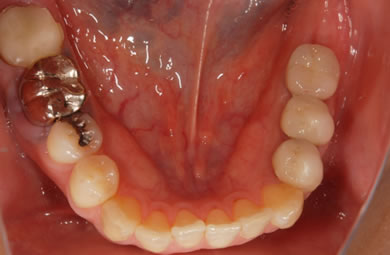

インプラントの症例写真 IMPLANT

インプラント治療+セラミック治療

| 治療方針 | 臼歯部の審美的・機能的回復をインプラント治療とセラミック治療にて行う。 | ||||||||||||||||||||||||||||||||

| 治療内容 | インプラント1本、メタルボンドセラミック2本 | ||||||||||||||||||||||||||||||||

| 総治療費 | 572,750円 | ||||||||||||||||||||||||||||||||

| 治療期間 | 3ヶ月 |